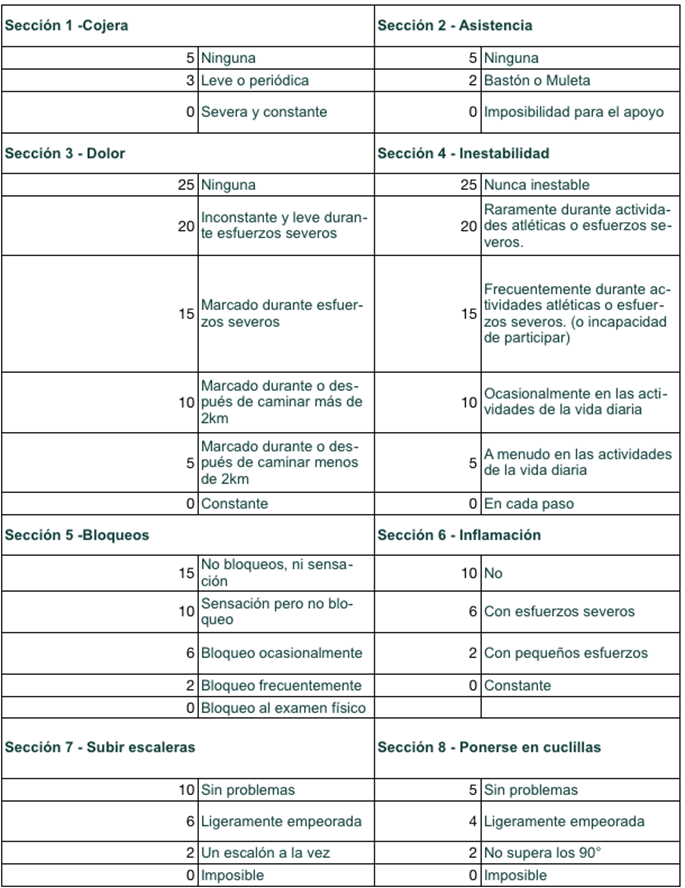

Tabla 1. Score de Tegner & Lysholm. Valora la capacidad funcional de la rodilla. Va de 0 a 100 puntos, pudiendo el resultado ser pobre (<65 puntos), aceptable (65-83), bueno (84-90) o excelente (>90)

Tabla 2. Score de IKDC (International Knee Documentation Committee). Valora 3 grandes elementos: síntomas, actividad deportiva y función/actividades de la vida diaria (AVD). Va de 0 a 100 puntos.

Tabla 2. (continuación) Score de IKDC (International Knee Documentation Committee). Valora 3 grandes elementos: síntomas, actividad deportiva y función/actividades de la vida diaria (AVD). Va de 0 a 100 puntos